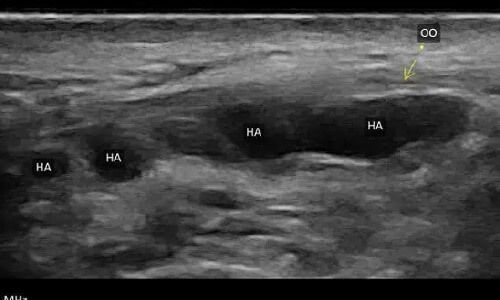

1.玻尿酸(Hyaluronic Acid)

超音波:

黑黑的(低回音),最好認。

困擾:

注射層太淺或劑量太多,常出現丁達爾效應(看起來透亮、偏藍灰)。

處理:

用超音波定位後,打玻尿酸酶把它分解。通常退得快,線條會回來。